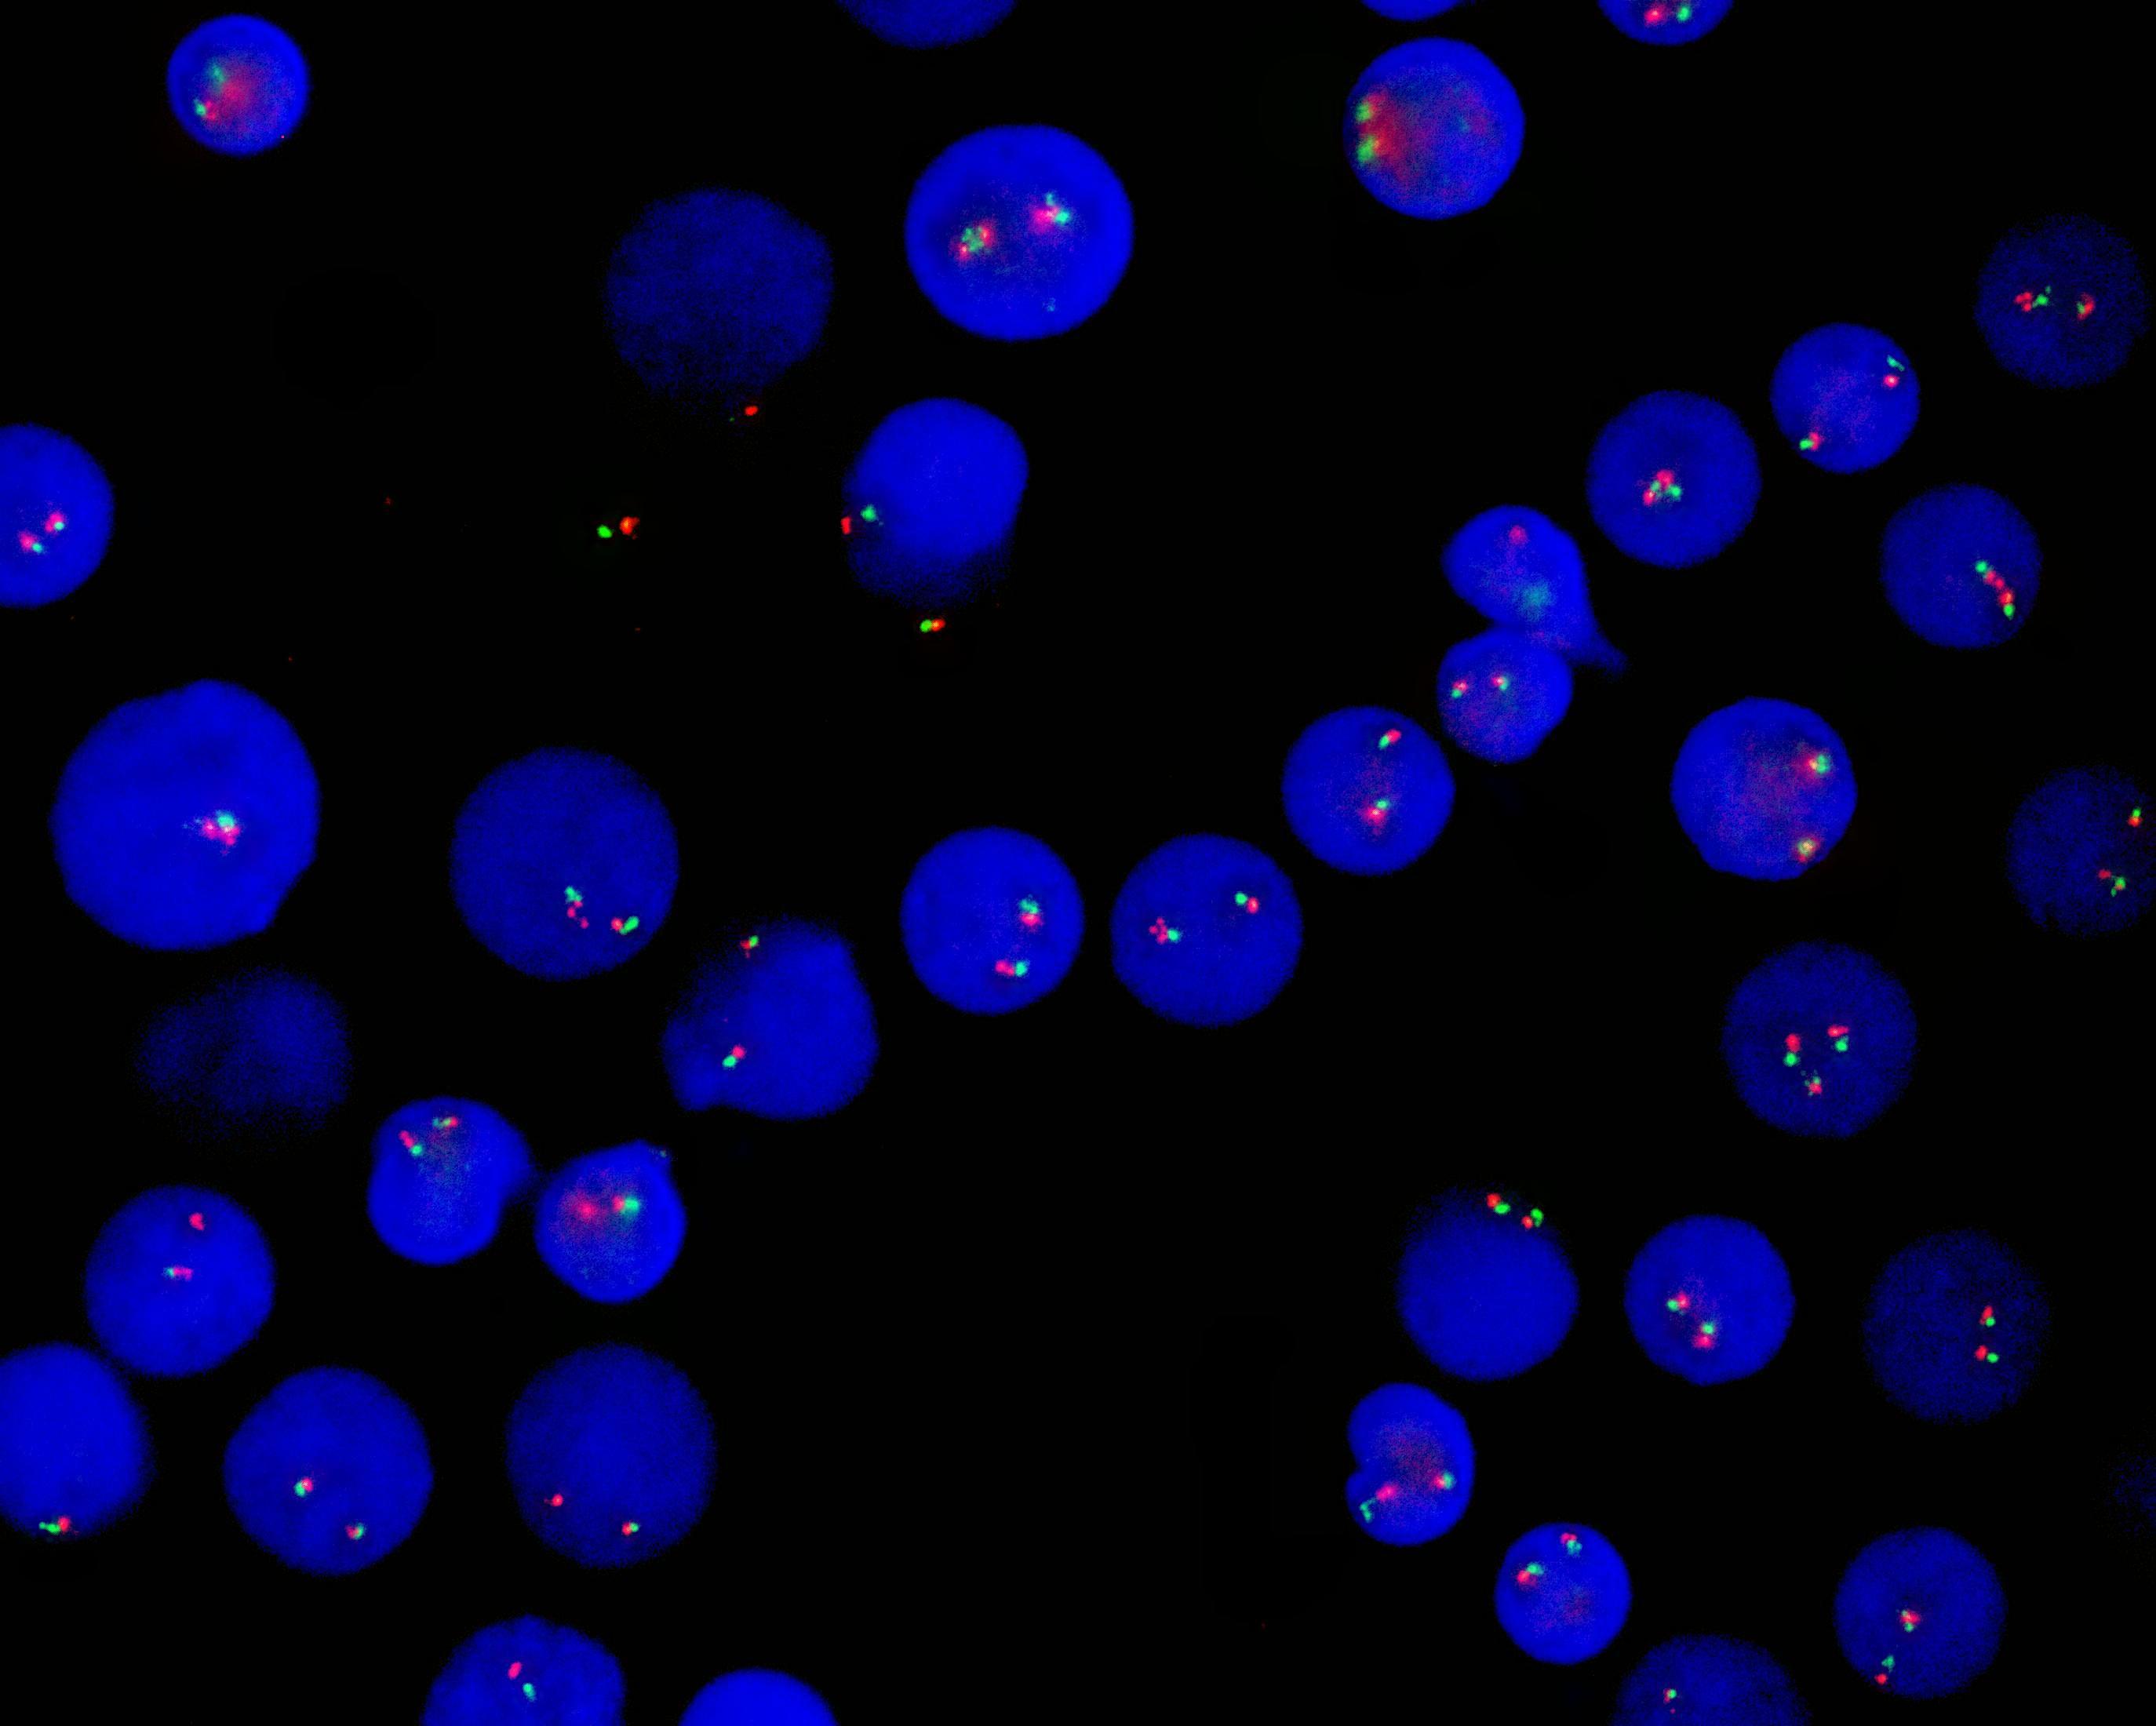

PDGFRA dual color probe(CHIC2缺失)探针

CHIC2 gene labeled as orange, with a length of 451 kb; PDGFRA gene labeled as green, with a length of 620 kb; FIP1L1 gene labeled as green, with a length of 701 kb.